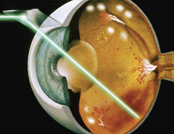

严格控制血糖丶血压丶血脂和定期做眼科检查对保护视力非常重要。一旦发现眼内有新生血管生长,或者黄斑点附近有水肿和渗漏,便须要安排眼内注射抗血管内皮生长因子或激光治疗,以保存视力。假如患者情况严重,如视网膜脱落丶眼内出血或持续黄斑水肿,玻璃体切除手术就能助其恢复视力。

![]() 糖尿病视网膜激光治疗 |